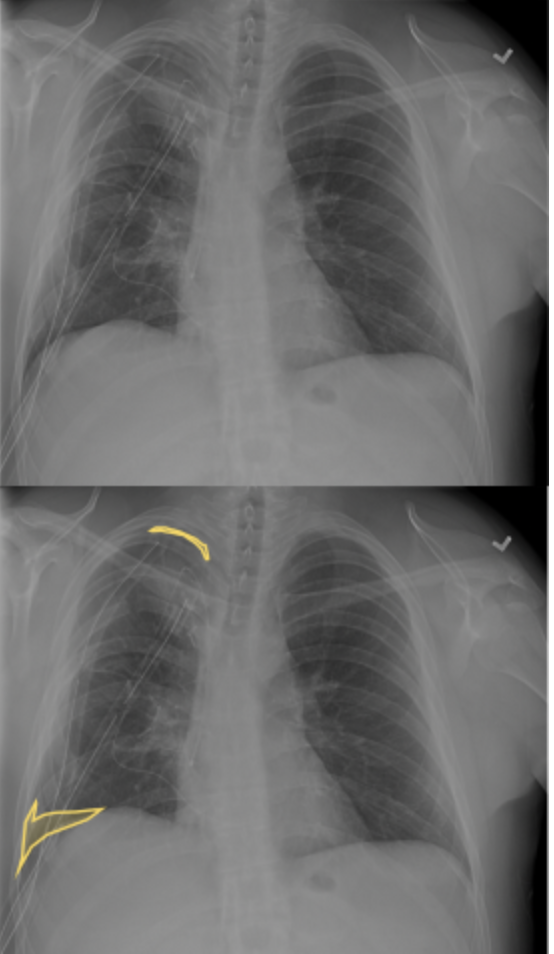

Slide 5

Some x-rays may show multiple areas of pneumothorax. Here we can see two different ones: at the top right and bottom right (anatomically).